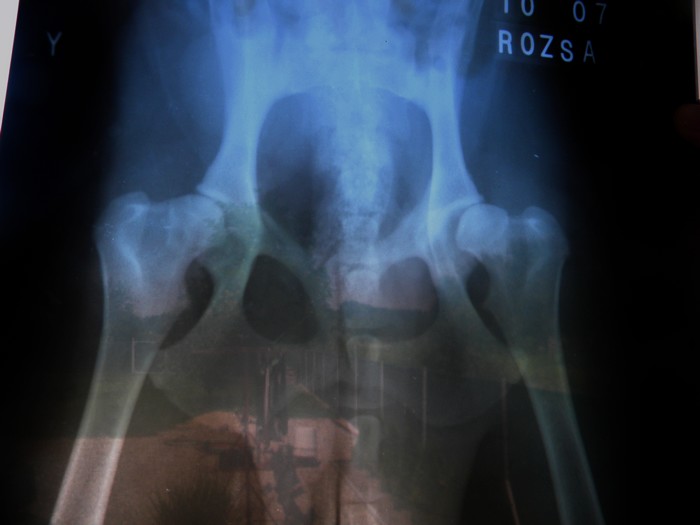

Mollynak diszpláziája van C/D besorolású

Hoztam az RTG-ről képet

A bal csípője C-s a jobb pedig D-s besorolásúnak megy el, tehát Mollynak mindkét felén eléggé kemény diszpláziája van, délután megmutatom a röntgen képet is